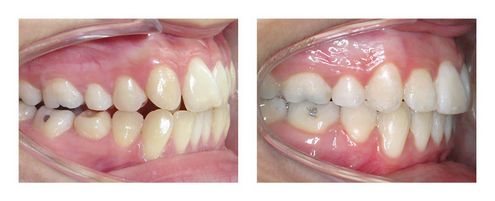

Cas Orthodontie Paris 4 : Alignement et élastiques d’un côté

Le motif de consultation était la mauvaise position de l’incisive supérieure, mais la patiente présentait également un excès de recouvrement incisif (incisives inférieures trop recouvertes par les incisives supérieures) et un décalage des arcades d’avant en arrière de 3 mm à droite (à gauche sur la photo). C’est le décalage des dents qui a été à l’origine des troubles de l’alignement des dents supérieures. Un contact trop fort entre les incisives du haut et du bas peut être à l’origine d’abrasions (usures) des incisives inférieures.

L’orthodontie a permis d’obtenir l’alignement espéré et surtout une occlusion fonctionnelle par nivellement des arcades et le port d’élastiques inter-arcades à droite. Les photos de fin présentées ici ont été prises 3 ans après la fin du traitement et montrent la stabilité. Le traitement a duré un an grâce au sérieux de la patiente.